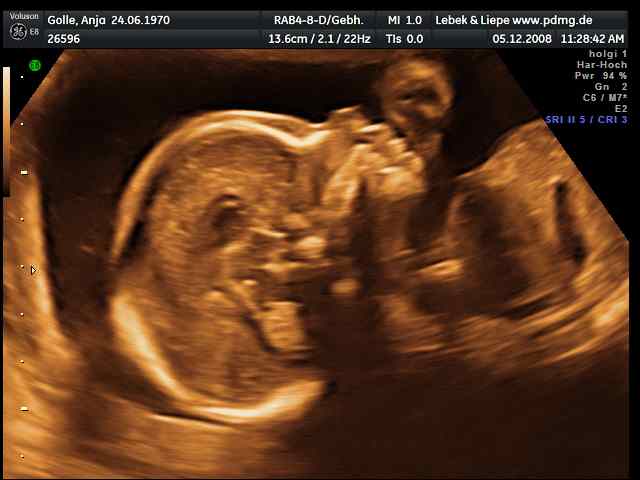

03/2006 => 1. IVM (D), POSITIV